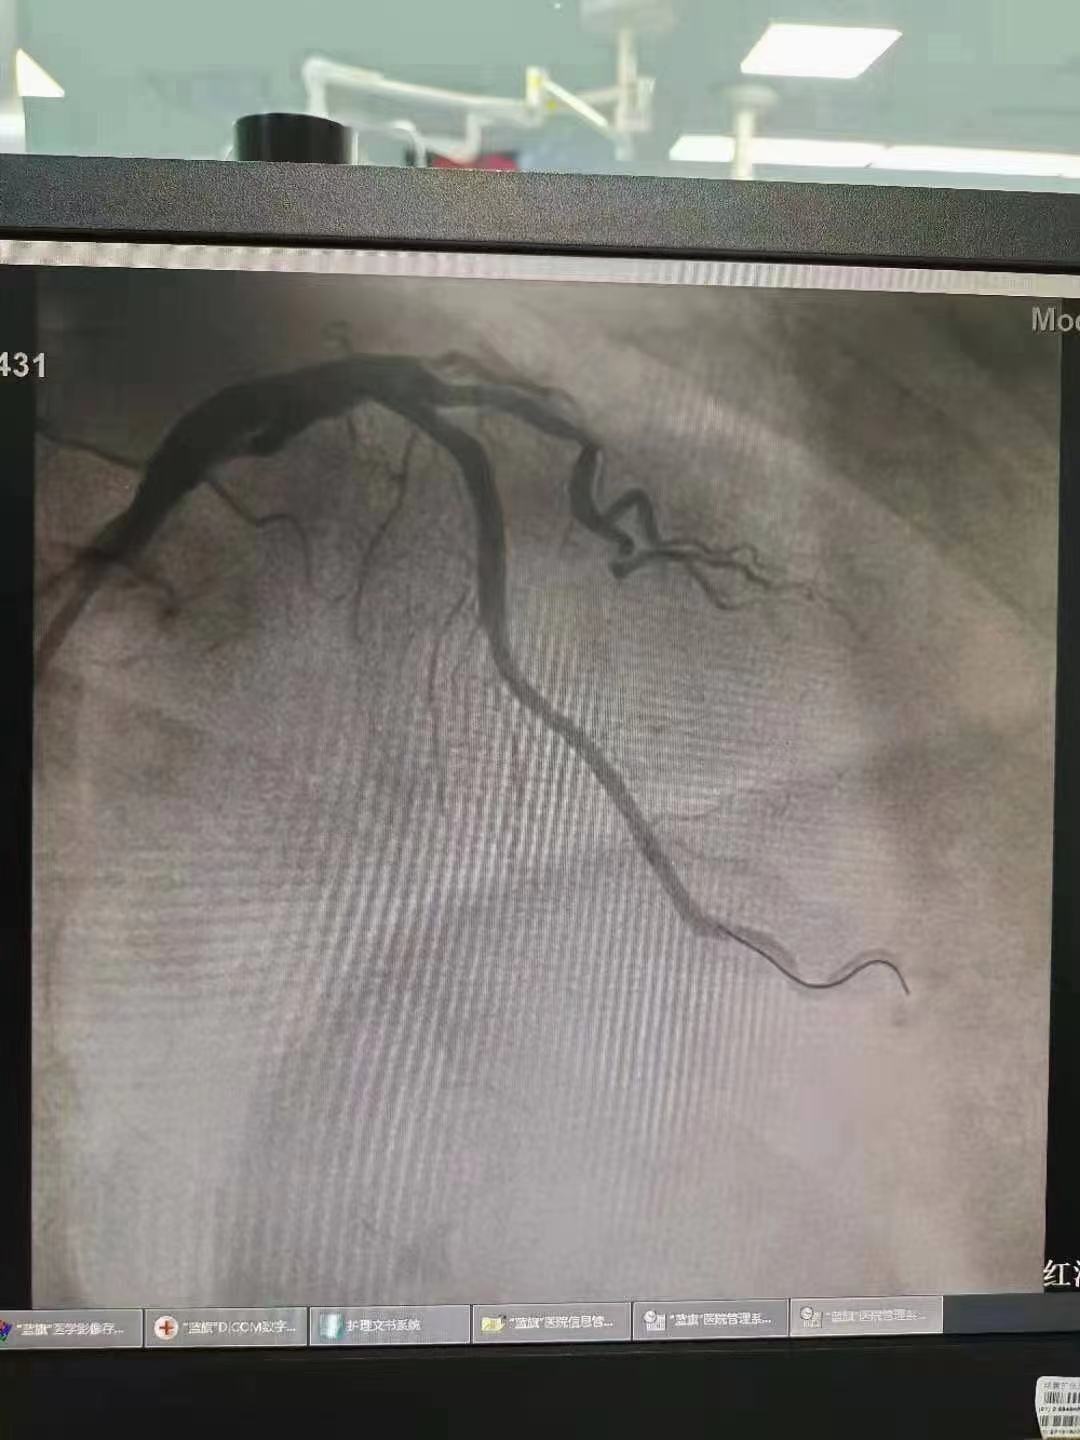

祝賀 云南省滇南中心醫院  黃銳團隊成功為患者植入3.5~15Xinsorb生物可吸收支架!